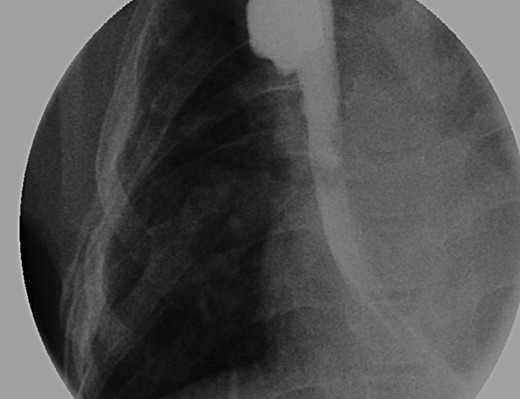

Daily tightening of her traction sutures was performed until the distal esophageal segment reached the chest wall (Fig. 2). The cervical esophagostomy was also sequentially lengthened and eventually internalized. Three traction suture revisions and two proximal esophageal lengthening operations were performed before esophageal continuity was re-established (46 days). Two subsequent anastomotic leaks occurred; 1 anastomotic leak was repaired surgically, whereas one subsequent leak was managed nonoperatively with a chest tube. Five dilations and, one, 13-day retrievable stent placement were needed for anastomotic narrowing. A comparative postoperative esophagram and intraoperative esophagram illustrated neither a stricture nor an anastomotic leak (Fig. 3). Total hospitalization was 112 days.

An intraoperative esophagram following a routine esophagogastroduodenoscopy (EGD) is pictured on the right, as compared with her postoperative esophagram on the left. The EGD was performed on this patient following her anastomosis (Foker Stage II); the native esophagus was now in continuity. Contrast was injected above the level of the anastomosis, which demonstrated neither leak nor stricture.